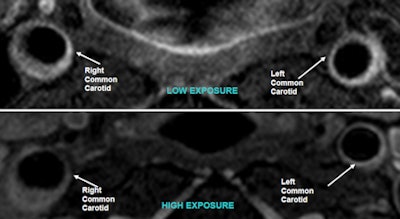

Dynamic contrast-enhanced MRI demonstrated that neovascularization, indicative of carotid wall inflammation and early arterial plaque development, was also more pronounced among workers exposed to more polluted air.

| Sample dynamic contrast-enhanced MR images of left common carotid arteries reveal extensive neovascular development in a high-exposure patient (right) compared to a low-exposure patient. Images courtesy of Venkatesh Mani, PhD. |